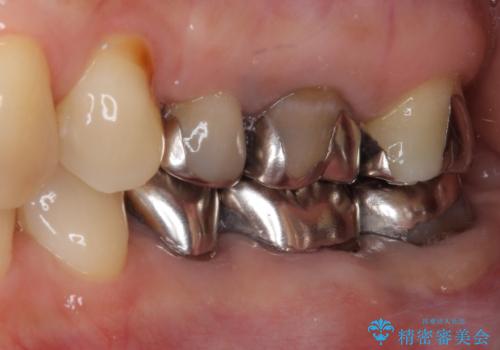

ブリッジの支台歯は2本とも神経を取り除いている歯であるため、咬合力の強い方ですと、支台歯も歯根破折をするリスクがあります。

今回はそれほど咬合力が強いとは思われなかったため、ブリッジによる補綴治療を行いましたが、念のため、就寝時にはナイトガードとしてマウスピースを装着するようお願いしました。